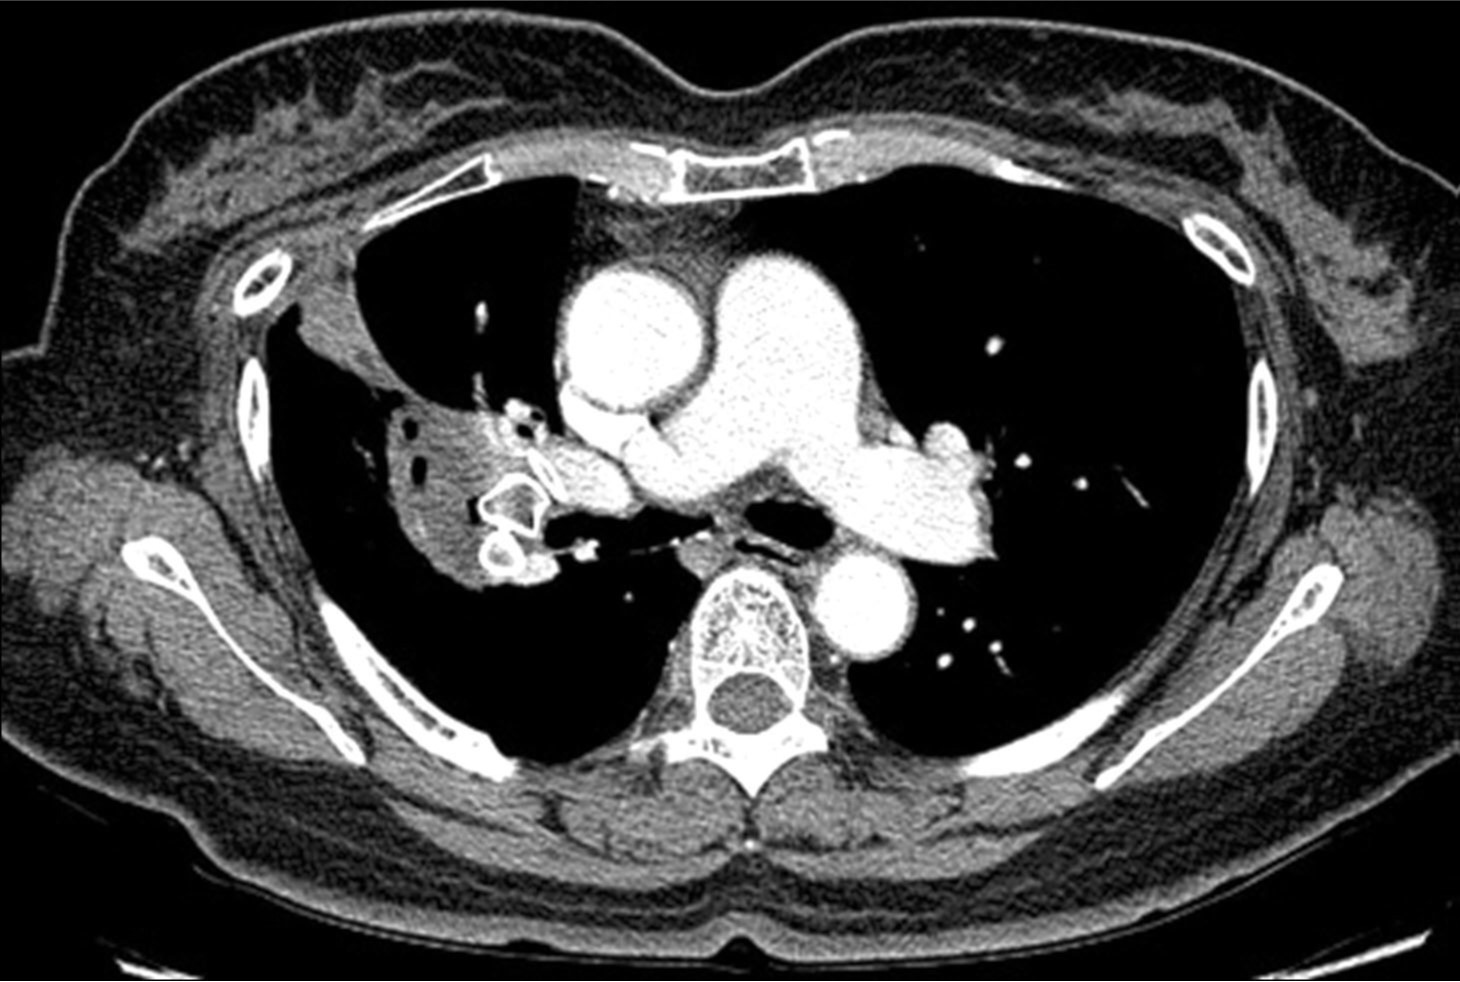

Fig. 1. B

Fig. 1A, B. The axial (A) and coronal (B) images of chest CT scan demonstrate a pseudoaneurysm (arrows) in the right lower lobe, connected to the proximal part of the right lower pulmonary artery.